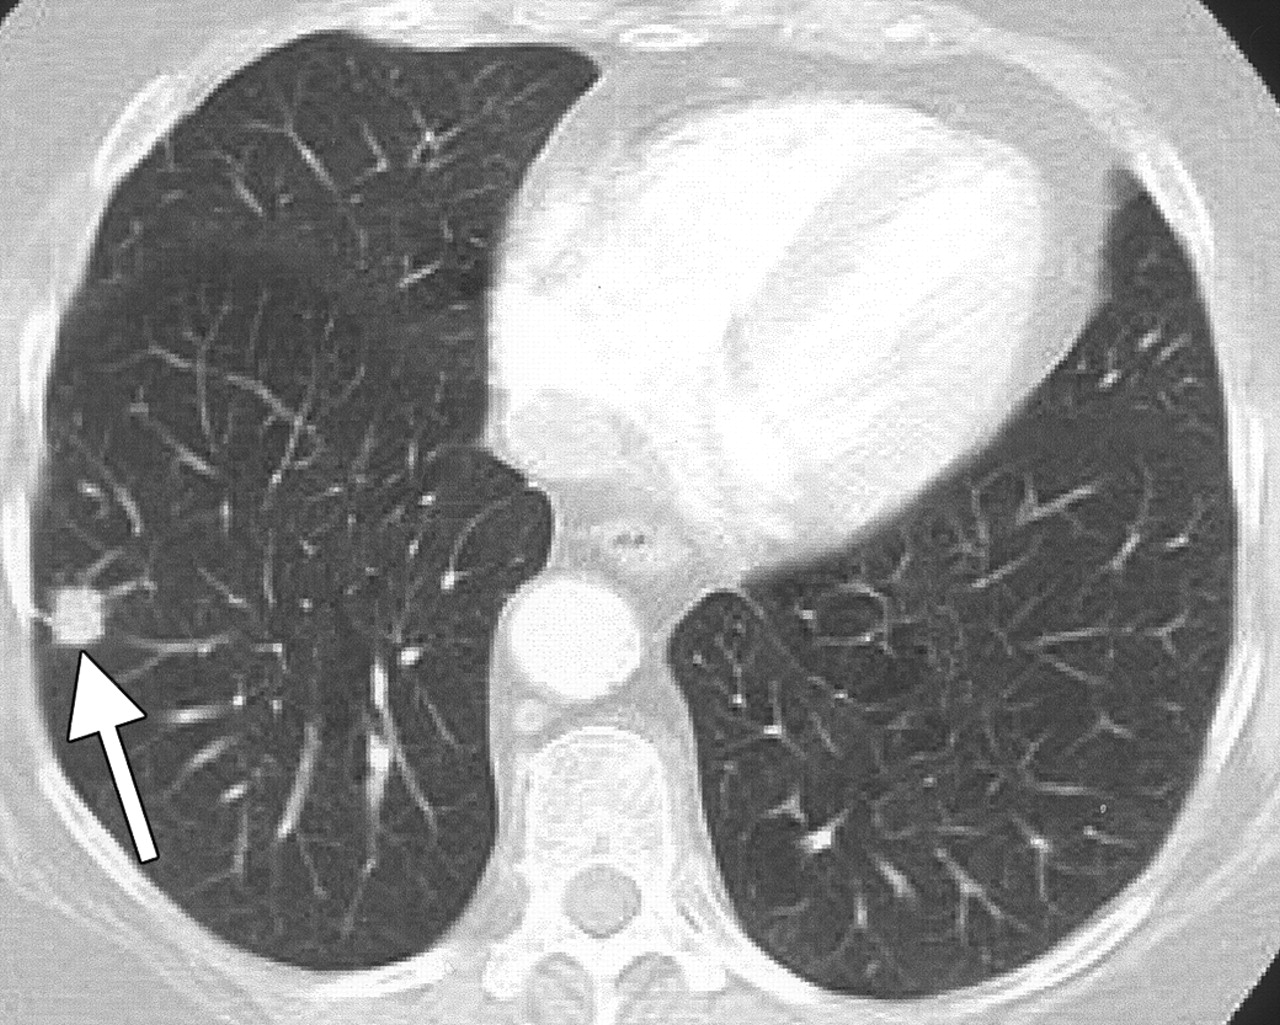

Фотографии и снимки КТ легких без контрастных веществ

Раздел: Визуальный дайджест